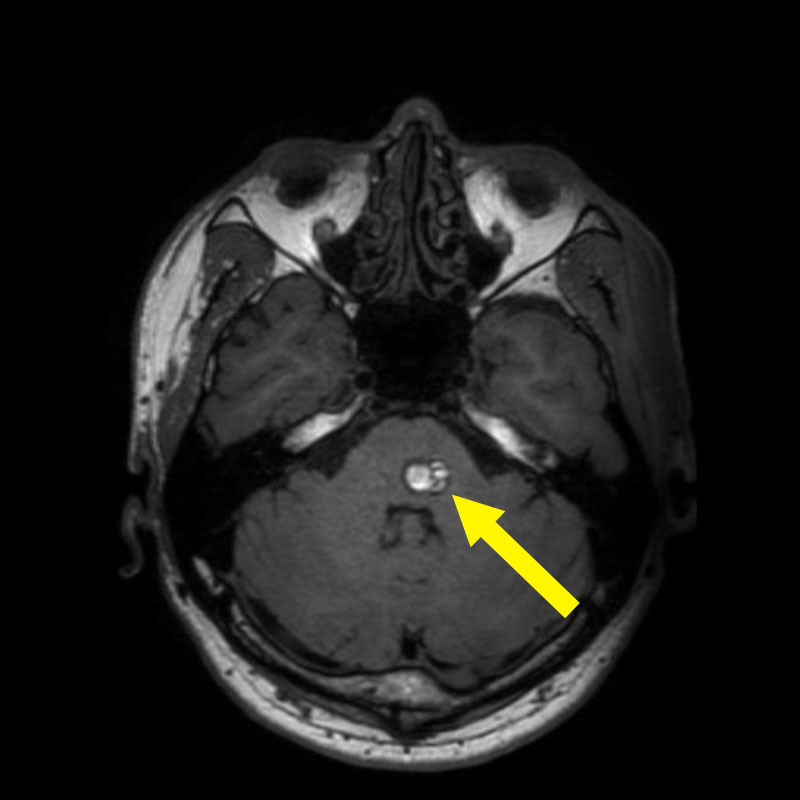

'19年11月

40代

富永

南田

基底核

海綿状血管腫

出血性

兵庫県の病院

より紹介

No.No.32 手術前1

No.No.32 手術前2

No.No.32 手術後1

No.No.32 手術後2

CT/MRにより完全に摘出されたことが確認された